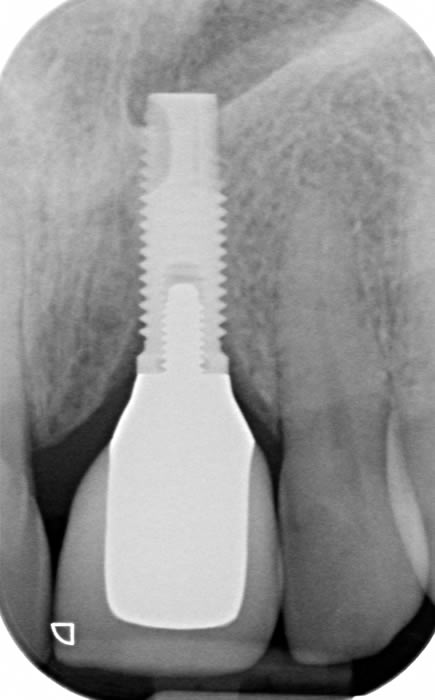

More front teeth replaced by dental implants

Case Three (4 images)